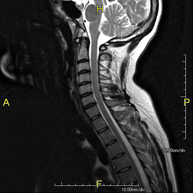

Esta prueba sirve para observar la médula espinal, las raíces de los nervios y las meninges. En ella, se utiliza la fluoroscopia, que es un tipo de radiografía en tiempo real junto con la inyección de un contraste.

Resultado de imagen de mielografia